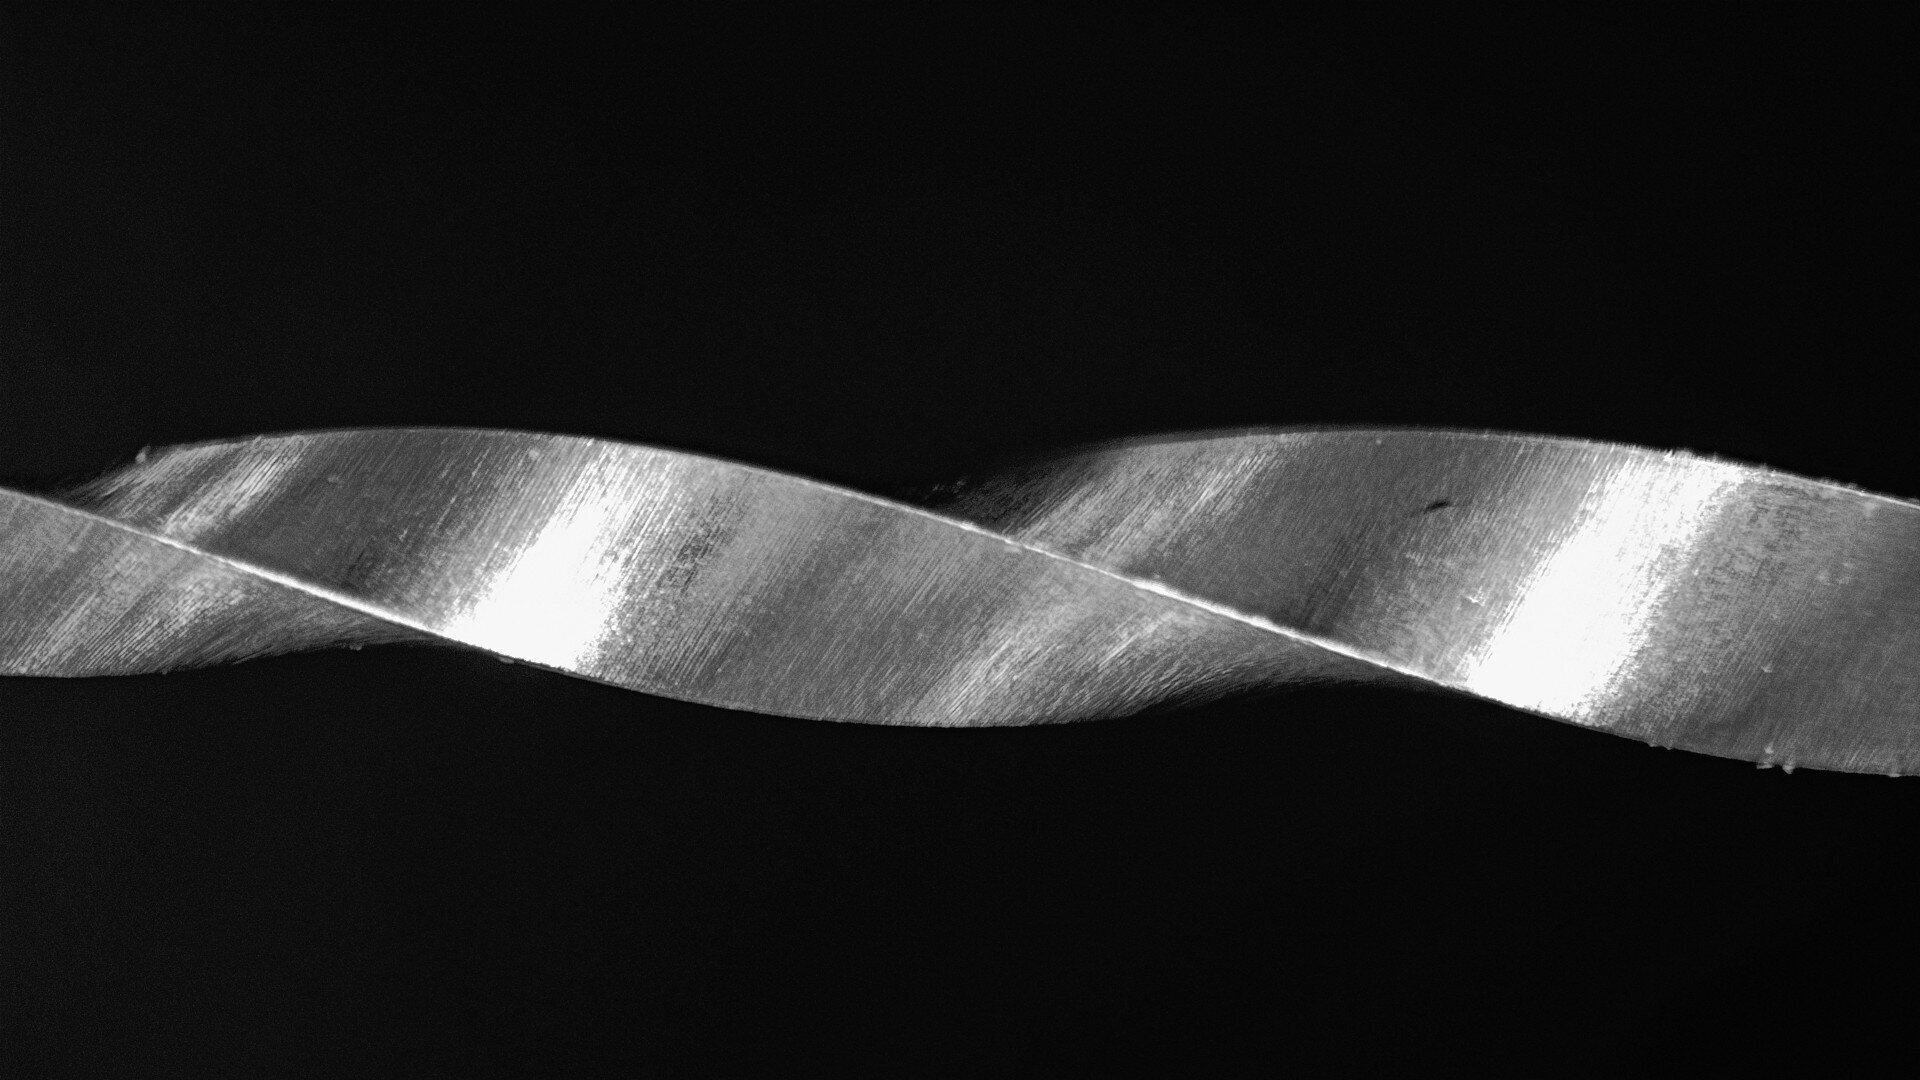

It all began with Twisted Files from Sybron Endo (today part of Kerr Dental)—the first time that heat treatment was applied to NiTi rotary files—starting a new chapter in root canal therapy. Years later, a different approach to heat treatment was introduced, allowing engineers to combine two distinct alloy structures within a single file. This innovation brought greater safety and built-in flexibility to rotary instrumentation. ZenFlex (Kerr Dental) is one such example, taking file technology to a new level with a fresh perspective.